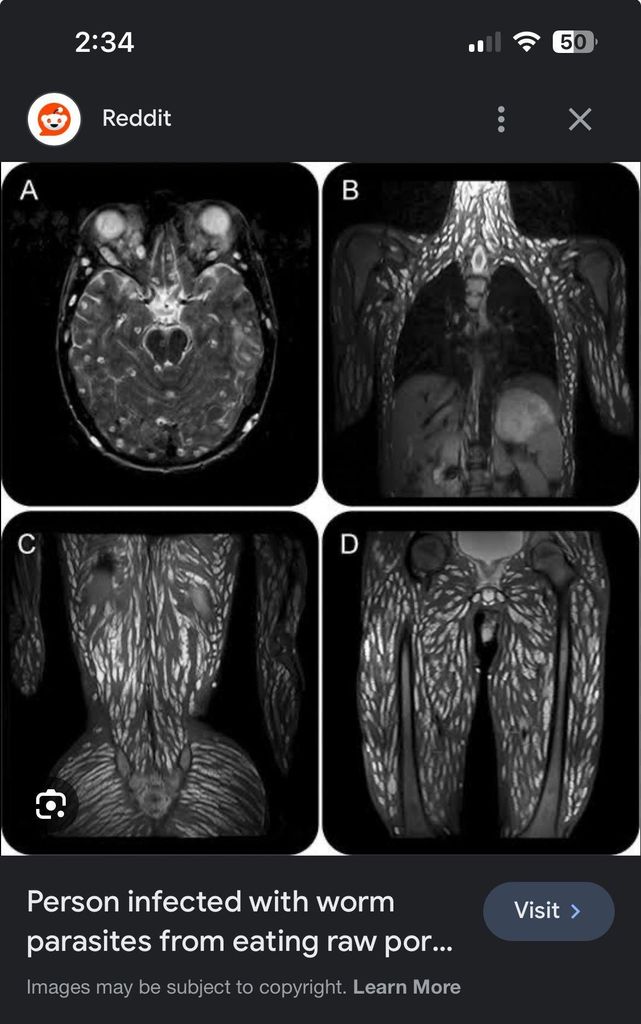

gore mental:

c'était une paysanne chinoise de la campagne, depuis ses 10 ans elle prenait le porc juste après sa mise à mort et elle le mangeait cash

meme dans le cerveau

comment c est possible

ils font quelle taille au debut ?